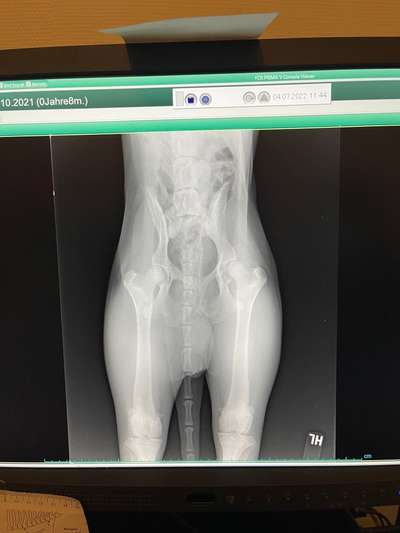

Hallo Zusammen, Mein Hund Tyson( 8 Monate alt )hat seit 3 Wochen Probleme mit seiner Hüfte.. ( Vorallem linke Seite )Bein laufen wackelt sie stark hin und her. Heute habe ich beim Tierarzt Röntgen Bilder von seiner Hüfte machen lassen. Mir haben sie gesagt dass ich in eine Spezialklinik in Duisburg fahren soll. Hat jemand Erfahrungen damit ? Oder vielleicht schonmal eine ähnliche Situation? Kann mir jemand weiterhelfen? :(

Die Röntgenbilder sind nicht gut, da der Hund nicht korrekt gelagert ist.

Ich hab schon viele Röntgenbilder gesehen. Könnte eine C Hüfte sein, da operiert man nicht!

Dazu sind die Bilder zu schlecht um es hier zu erkennen.

Uii das sieht aber nach einer starken HD aus 😔 geht zu einem Experten und lasst euch beraten, dein Schnuff hat sicher arge Schmerzen.

Ja, bin kein Experte, aber es sieht aus als hätte der Hund beim Röntgen schief gelegen.

Und genau abklären was das ist, also neue Röntgenbilder machen und einen Experte soll das beurteilen.

Könnte er sich ausgetenkt haben? Ich seh nämlich auf dem röntgenbild auch so schief aus... Vlt mal zum Chiropraktik mit dem hund